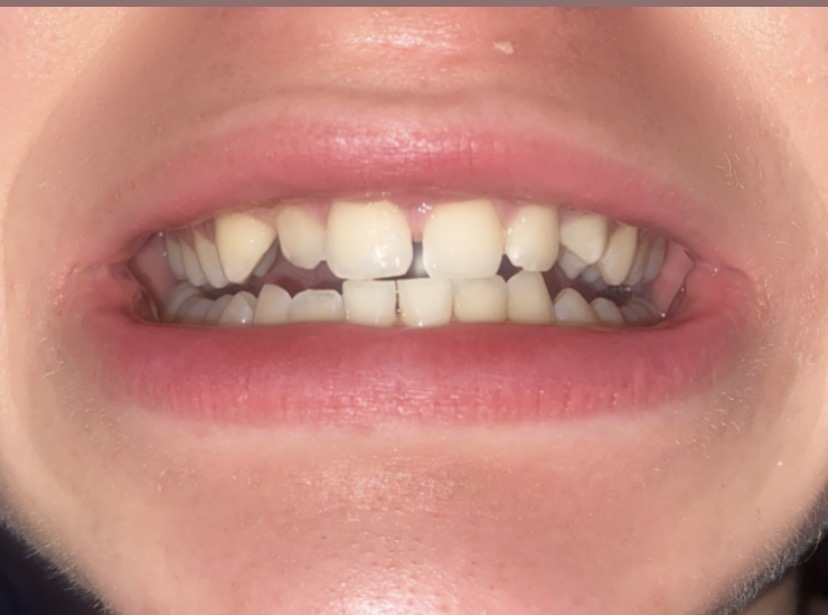

Have an ortho visit soon. Any advice before hand on what I need to get fixed, I have a cross bite and crooked teeth. Your not medical professionals but do you have advice if I should do orthtropics or dontics

IMG 0955